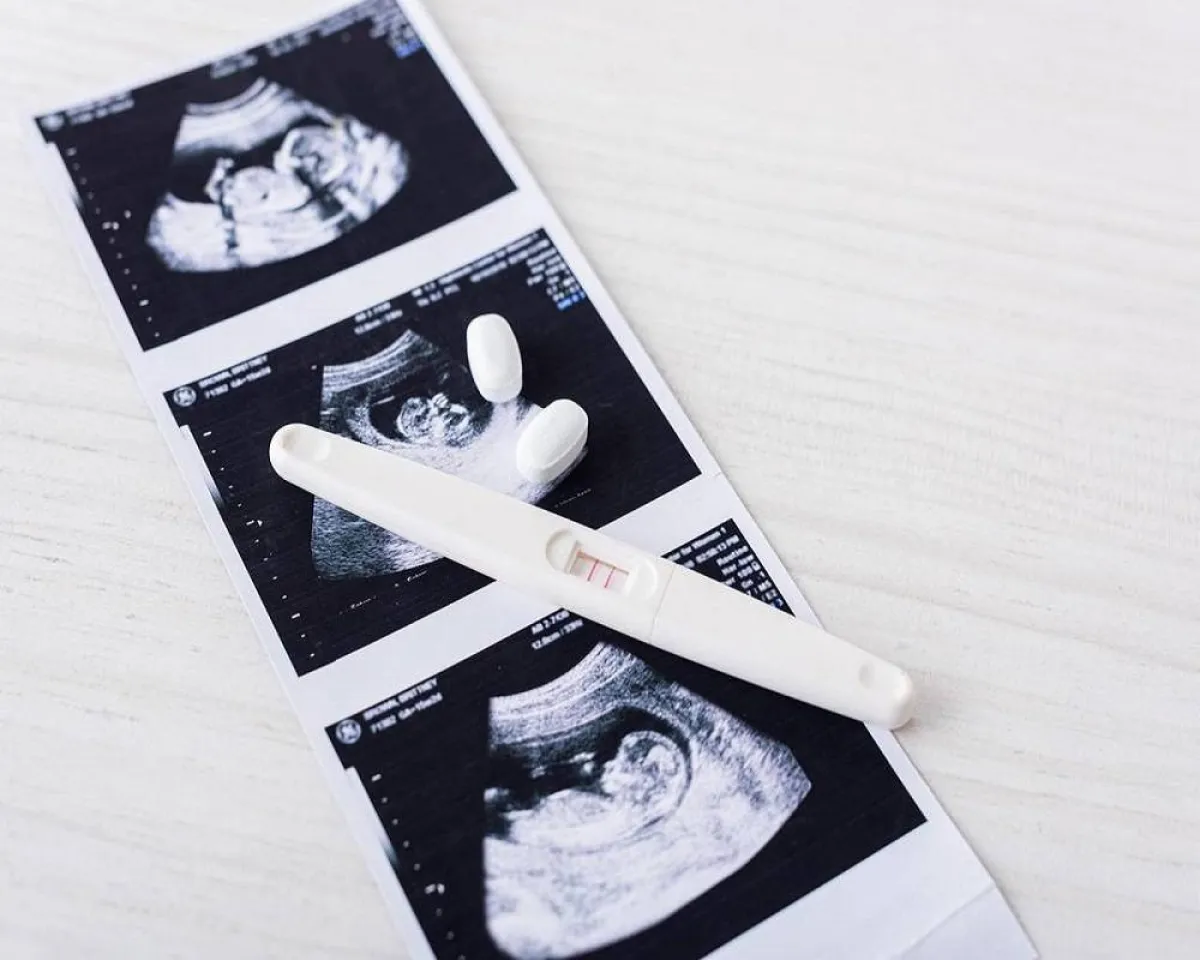

كثيرة هي الطرق التي يستخدمها الأطباء لمعرفة نوع المولود في الأسبوع العاشر من الحمل ويمكن أن يكون ذلك من خلال الموجات فوق الصوتية في الفترة من 19 إلى 20 أسبوعاً .

وتعد أكثر الطرق الموثوقة للتنبؤ بنوع الجنين هي الموجات فوق الصوتية التي يتم إجراؤها بعد 14 أسبوعاً من الحمل أو الاختبارات الجينية مثل تلك التي يتم إجراؤها أثناء فحص السائل الأمنيوسي أو أخذ عينات من الزغابات المشيمية (CVS) أو اختبار الدم غير الجراحي قبل الولادة (NIPT).

وفقا لموقع "PubMed"يمكن للحامل معرفة نوع المولود في الأسبوع العاشر بمجموعة من الاختبارات والفحوصات. فيما يلي بعض الطرق الممكنة: